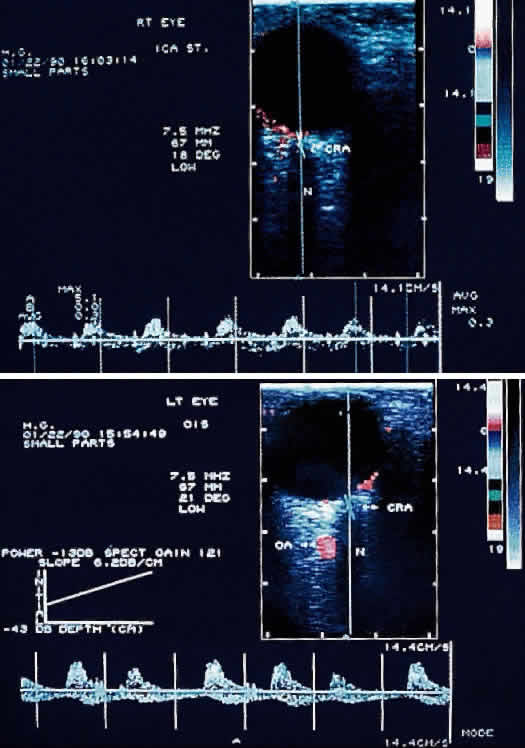

Orbital color Doppler imaging is a noninvasive ultrasound test that permits simultaneous imaging of small orbital vessels and recording of quantitative data on blood flow velocity. Unlike duplex carotid ultrasonography, which images and measures flow velocity in the large carotid vessels, orbital color Doppler imaging can image the smaller ophthalmic, central retinal, and short posterior ciliary arteries.28

With the use of orbital color Doppler imaging, the central retinal and posterior ciliary artery peak systolic velocities have been reported to be markedly reduced in ocular ischemic syndrome, as would be expected (Fig. 8).13 Reversal of ophthalmic artery blood flow, which probably represents collateral blood flow to lower resistance vascular beds, was detected in 75% of eyes with ocular ischemic syndrome. It is interesting to note that although high-grade carotid stenosis, reversal of ophthalmic artery flow, and decreased central retinal artery flow have been associated with ocular ischemic syndrome, this combination in and of itself has not been sufficient to routinely produce decreased vision. Absence of detectable posterior ciliary arterial blood flow was the only reliable indicator of poor vision.

Fig. 8. Color Doppler imaging study of the central retinal artery in an eye with ocular ischemic syndrome (left). Areas in red superimposed on the B-scan image depict blood flow moving toward the transducer, mostly representing arterial flow. Areas in blue depict flow, mostly venous, away from the transducer. Notice the reduced systolic peaks of the time-velocity waveform (graph below the B-scan image) in contrast to the normal pattern of the uninvolved contralateral eye (right). (Ho AC, Lieb WE, Flaharty PM et al: Color Doppler imaging of the ocular ischemic syndrome. Ophthalmology 99:1453, 1992)